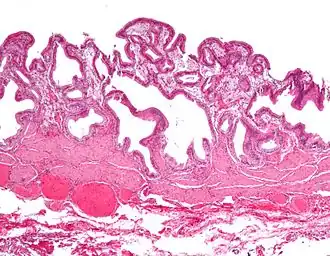

En medicina, la colesterolosis vesicular es la acumulación focal de histiocitos espumosos (macrófagos) cargados de colesterol en la lámina propia de la vesícula biliar.[1]

A veces se llama vesícula biliar de fresa por el aspecto punteado de la superficie de la mucosa en un examen general, similar al que presentan las fresas. La colesterolosis está causada por una acumulación anormal de depósitos de ésteres de colesterol en macrófagos dentro de la lámina propia (células espumosas) y en el epitelio de la mucosa. La vesícula biliar puede estar afectada de forma localizada o de forma difusa. La forma difusa se presenta macroscópicamente como una mucosa roja brillante con motas amarillas (debido a los lípidos), de ahí la comparación con la fresa. No está ligada a la colelitiasis (cálculos vesiculares) ni a la colecistitis (inflamación de la vesícula biliar).[2]

Colesterolosis de la vesícula biliar (imagen bruta) -

Micrografía de colesterolosis de la vesícula biliar -

Micrografía de colesterolosis de la vesícula biliar